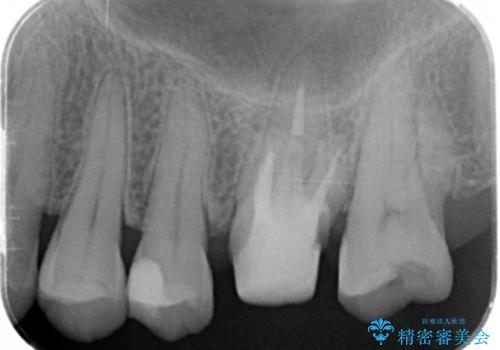

- 検査の結果被せ物の下に虫歯が確認された患者様です。

虫歯を取りきった後セラミッククラウンでの修復処置を行います。

被せ物の裏側の虫歯は被せ物を取らないと除去できません。

今回は過去に治療された部分をすべてやり直しました。

再治療にならないような精密な治療が重要です。